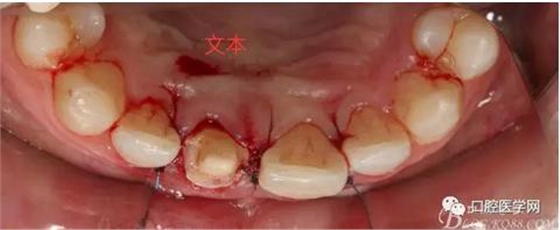

翻瓣 見11釉牙骨質(zhì)界存在,牙槽嵴頂?shù)接匝拦琴|(zhì)界不足2mm。21牙槽嵴頂?shù)接匝拦琴|(zhì)界不足2mm

去骨后,牙槽嵴頂?shù)接匝拦琴|(zhì)界達(dá)到2.5mm。保留11,21之間的牙槽嵴頂,不改變齦乳頭的狀態(tài)。